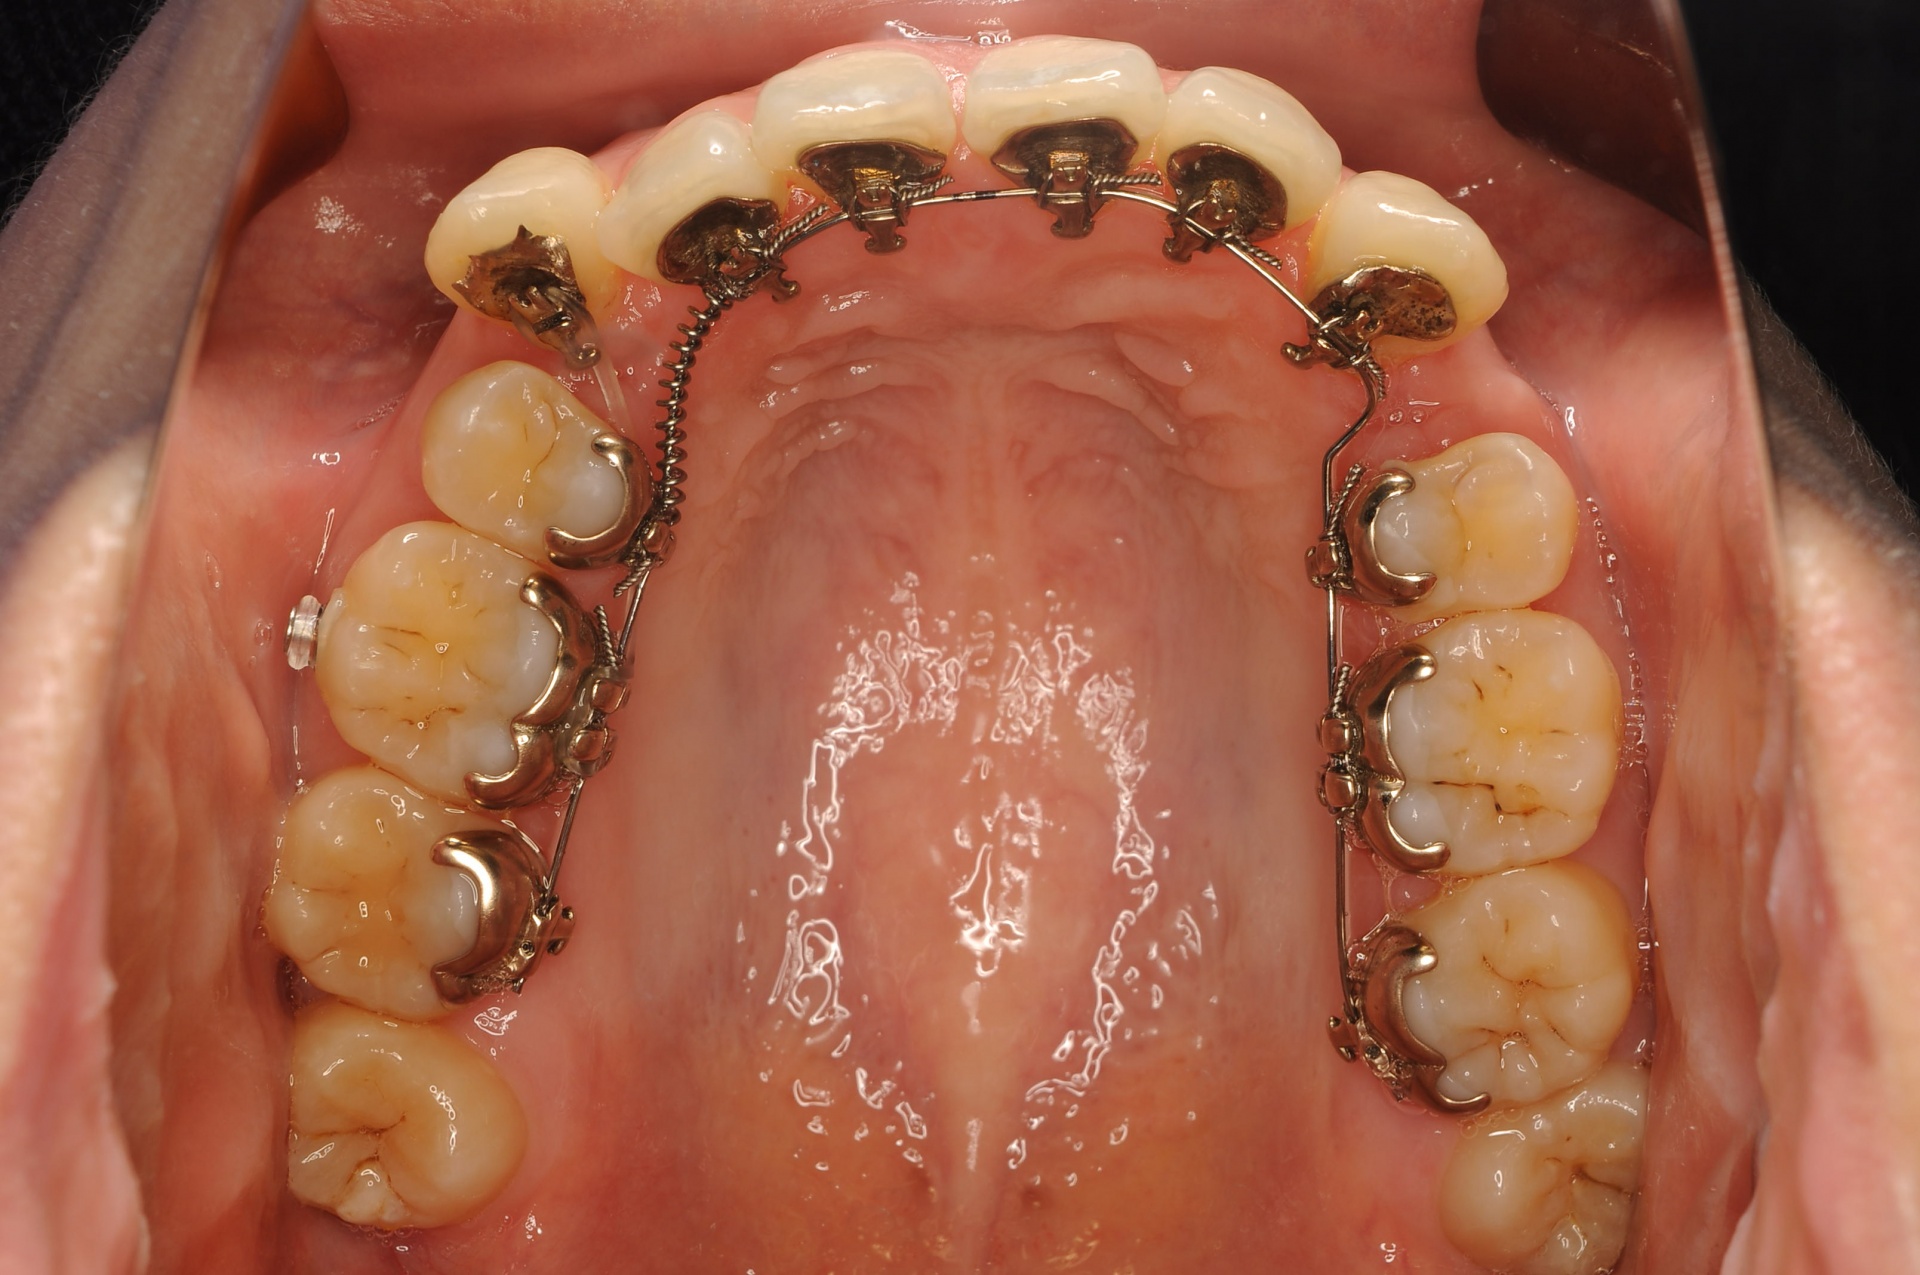

治療中

見えない装置(裏側矯正)を希望されましたので、上顎は裏側に装置をつけて、下顎はセラミックの白い装置としました。上顎両側犬歯を小臼歯の抜歯したスペースへ移動させました。下顎は非抜歯で叢生を改善しました。